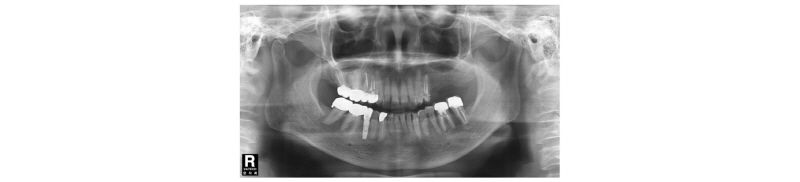

57세의 여성 환자로 기존 브릿지 보철 수복물(#24-27)의 상악 좌측 제 2대구치의 심한 우식으로 인해 내원하여 해당 치아를 발거하였다(Fig. 1). 상악 좌측 제 1 소구치는 근관치료를 시행한 후 보철 수복하기로 하였고 기존 pontic 부위였던 좌측 제 2 소구치와 발거된 제 2 대구치 부위에 #25i, #27i 2개의 임플란트 식립을 통한 브릿지 보철 수복물을 계획하였다(Fig. 2). 기존 pontic으로 유지되었던 좌측 제 2 소구치 부위는 치조제의 심한 수평적 치조골 흡수를 구강 내 임상검사를 통해 확인할 수 있었다. 전층 판막 형성후 상악 좌측 제 2 소구치 부위의 치조정 폭경은 약 2 mm 정도로 측정되었다(Fig. 3, 4). 치조골의 구개측에 약 1 mm의 치조골이 남도록 high speed carbide round bur를 이용하여 치조정에 horizontal intraosseous groove를 형성하였고 협측골의 근심, 원심측에 2개의 vertical intraosseous groove를 형성하였다(Fig. 5). Chisel과 ridge spreader drill (RS kit, Dentium, Korea)을 이용하여 점차적으로 협측 골판을 구개측으로부터 분리시켰다(Fig. 6). Osteotome을 이용, 식립 깊이까지 적용하여 임플란트 식립 부위를 형성하였고 Ø4.3 × 10 mm (Implantium, Dentium, Korea) 임플란트를 식립하였다(Fig. 7). 발치 후 치유된 상악 좌측 제 2 대구치 부위는 상악동 거상술(수직 접근법)을 시행, 골이식을 한 후 4.8 × 10 mm (Implantium, Dentium, Korea)를 식립하였다(Fig. 8). 이후 이종골 이식재(Bio-Oss®, Geistlich, Switzerland)를 식립된 임플란트와 협,구개 측 치조골판 사이의 gap과 협측골판 상방에 적용하고 흡수성 교원질 차폐막(Bio-Gide®, Geistlich, Switzerland)로 피개한 다음 감장절개를 통해 장력없이 봉합하였다(Fig. 9-11). 이후 구강 내 검사 및 방사선 검사를 통해 수술부위 치유상태를 확인하였고 특이한 임상적 소견없이 정상적으로 잘 치유되었다(Fig. 12). 약 3개월 10일 정도의 치유기간 후 이차수술을 시행하였다(Fig. 13). 판막 거상 후 치조제 분할술을 시행하였던 상악 좌측 제 2 소구치 부위에 잘 형성된 신생 골양조직이 관찰되었다(Fig. 14). 상악 좌측 제 2 소구치 부위와 상악 좌측 제 2 구치 부위에 치유지대주를 장착하였고 상악 좌측 제 1 대구치 부위에 추가적으로 임플란트를 1회법으로 식립하였다(Fig. 15). 이차수술 이후 정상적으로 치유가 진행되어 약 2개월 후 최종 보철물 수복을 하였다(Fig. 16, 17). 약 1년 정도의 follow-up시 구강 내 검사와 방사선 검사를 통해서 임플란트 주위 연조직과 변연골이 잘 유지되고 있음을 확인하였다(Fig. 18).

Fig. 2. Pre-Op. Panoramic x-ray view. |